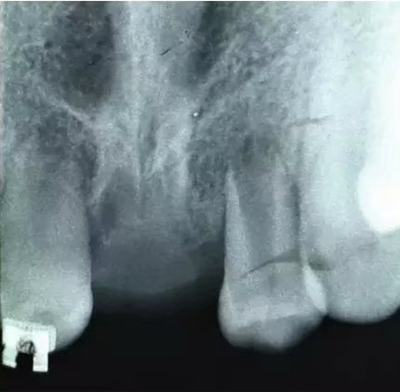

初步正畸牽引嵌入的上頜側(cè)切牙并重新獲得切牙空間。上頜側(cè)切牙的預(yù)后顯示有嚴(yán)重的牙根吸收。因此需要拔除上頜側(cè)切牙(圖3)。

圖3. 影像學(xué)顯示上頜側(cè)切牙牙根吸收